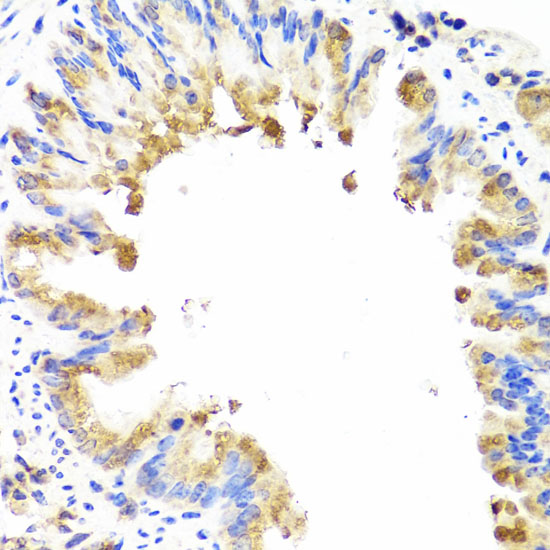

Immunohistochemistry of paraffin-embedded rat lung using AMBRA1 antibody.

Immunohistochemistry of paraffin-embedded mouse lung using AMBRA1 antibody.